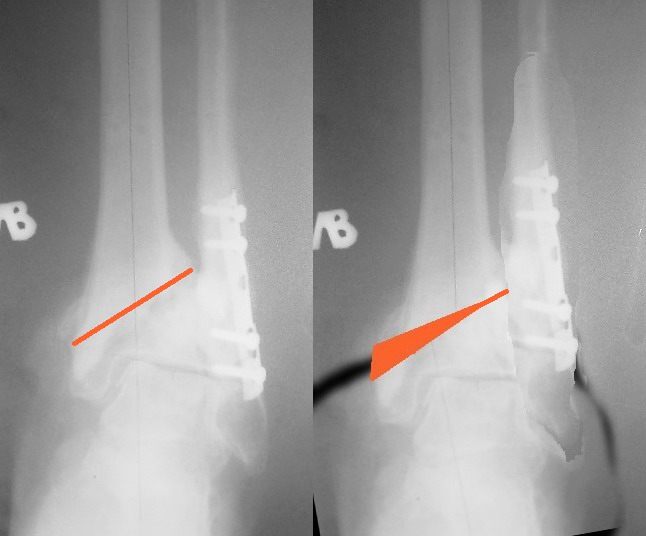

Чем вызвана такая деформация? Если это выраженный остеопороз, то вариант

видимо только один - артродез, если это - нестабильный

остеосинтез+несоблюдение ограничения нагрузки в послеоперационном периоде -

то видимо два. )))

Что касается голеностопного сустава - сустав вполне интактен в данном случае

(ИМХО), а изменения в нем вызваны вышестоящими проблемами.

Насчет дефекта кости. При первой операции он был вызван разрушением мягкой

спонгиозной кости при травме и сейчас не так актуален, если  не гнаться за

полным анатомическим восстановлением кости. Обычно дефект возникает не с

медиальной стороны, а в середине, а у вас при низведении сустава появится

дефект с медиальной стороны, под пластиной (на снимке).